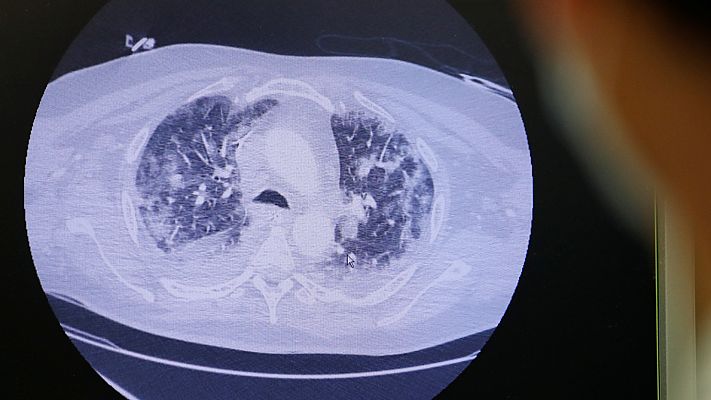

En Francia revisan pruebas que podrían indicar que ya hubo casos de coronavirus a mediados de noviembre

La OMS ha pedido a los países que revisen las historias médicas de pacientes para determinar cuándo empezaron los primeros casos de coronavirus....